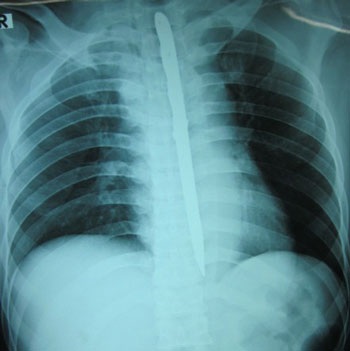

Kết quả chụp X-quang cho thấy hình ảnh con dao nằm trọn trong lồng ngực bệnh nhân. Rất may là con dao sau khi chui qua họng, chọc thủng thực quản xuống ngực, gây đứt vài mạch máu phụ của động mạch chủ ngực nhưng lại không gây tổn thương đến tim và các mạch máu lớn. Vì thế bệnh nhân may mắn thoát chết.